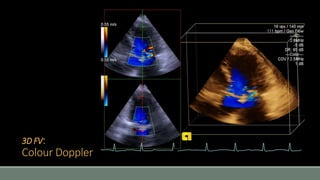

3D FV:

Colour Doppler

• #32 If we want to image the full volume, which means the volume within the whole angle of steering capacity, then it will be constructed from thin volumes acquired during consecutive cardiac cycles. This will need a trigger, typically ECG. Then the sub-volumes will be “stitched” together to produce the full dataset. Obviously this process can create artefact, mainly from respiratory movements and arrhythmia. Once obtained, the 3D full volume dataset is a big chunk of data that can be processed to display different types of views. The last mode is when colour Doppler is superimposed to the 3D pictures, just like it happens in 2D imaging.

• #39 Finally, colour Doppler data can be added to the 3D volume views, to offer a more complete view of the blood flows and jets across the valves.

• #40 Potentially, 3D can offer a better view of the anatomy of the jets, that would otherwise be assumed to be circular and may be underestimated. Complex jets can be properly visualized, for example complex paravalvular leaks.